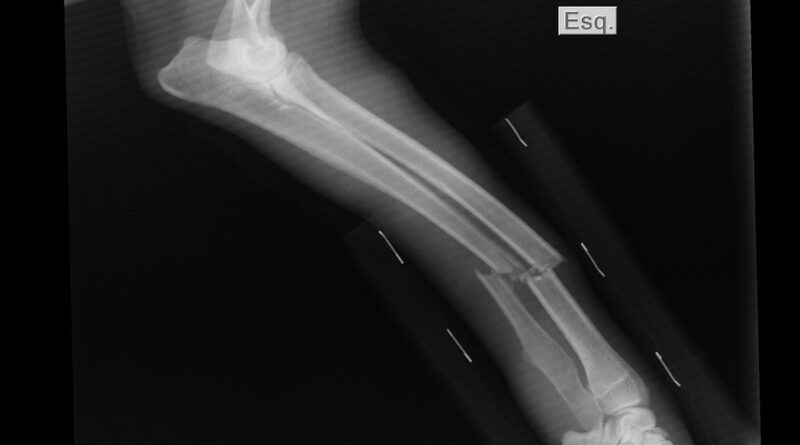

Osim bola, mogu se javiti i drugi lokalni simptomi. To uključuje otok, osjetljivost ili pojavu kvržice na određenom dijelu tijela. U nekim slučajevima dolazi do slabljenja strukture kosti, što može rezultirati prijelomima koji se dešavaju pri minimalnom opterećenju ili bez jasnog uzroka. Takve situacije zahtijevaju dodatnu medicinsku obradu.

Dijagnostika oboljenja kostiju obično započinje osnovnim pregledom i razgovorom s ljekarom. Nakon toga se, po potrebi, koriste metode snimanja poput rendgena, magnetne rezonance ili CT pregleda, koji mogu pokazati promjene u strukturi kosti. U određenim slučajevima, dodatne analize, uključujući uzimanje uzorka tkiva, koriste se kako bi se dobila tačna dijagnoza. Sve ove procedure sprovode se isključivo uz stručni nadzor.